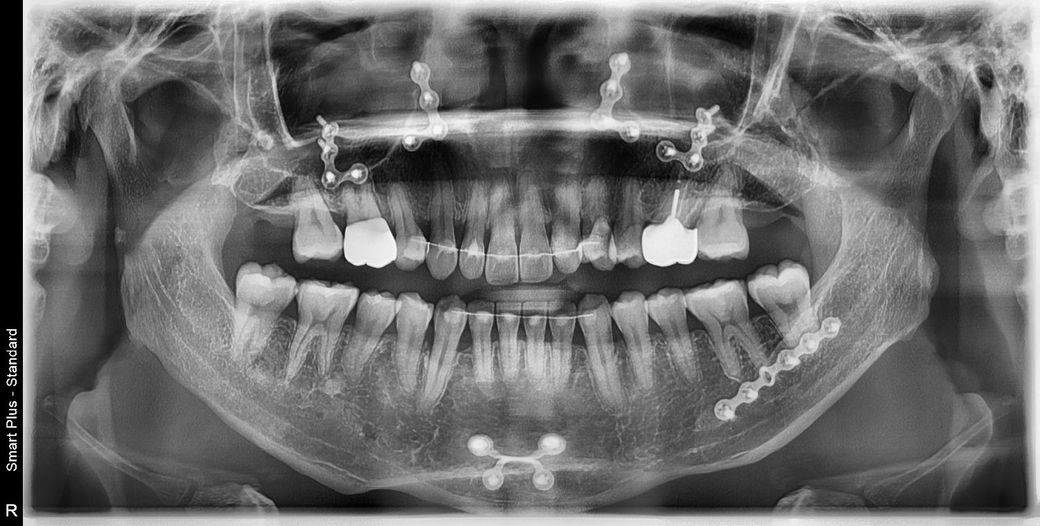

사진을보면 철사가 있을때는 제눈엔 안벌어진걸로보이거든요? 아닌가요? 제 기억에도 안벌어졌었고 철사가있을때 이미벌어져있었다면 그때알았을거고 철사제거할때 더욱 신중했을거거든요

이미 벌어진부분이있는곳에 철사를 완전제거를한다? 말이안되잖아요

• 2번 째 사진